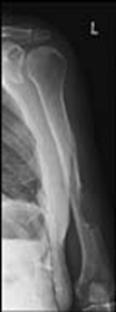

TRAUMATISMELE EXTREMITATILOR

Fractura de humerus

Fractura Monteggia Fractura 1/3 proximala radius si ulna Fractura proximala intracapsulara

de humerus

Fractura proximala

intracapsulara de humerus Fractura proximala intracapsulara de humerus